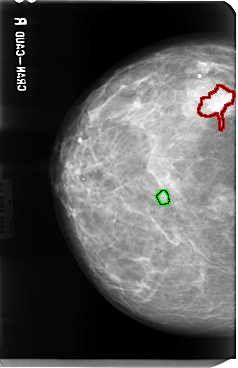

RIGHT_CC LINES 4784 PIXELS_PER_LINE 3088 BITS_PER_PIXEL 12 RESOLUTION 50 OVERLAY

FILE: B_3040_1.RIGHT_CC.OVERLAY

TOTAL_ABNORMALITIES 2

ABNORMALITY 1

LESION_TYPE MASS SHAPE IRREGULAR MARGINS SPICULATED

ASSESSMENT 4

SUBTLETY 4

PATHOLOGY MALIGNANT

TOTAL_OUTLINES 1

BOUNDARY

ABNORMALITY 2

LESION_TYPE MASS SHAPE OVAL MARGINS CIRCUMSCRIBED

ASSESSMENT 3

SUBTLETY 3

PATHOLOGY UNPROVEN